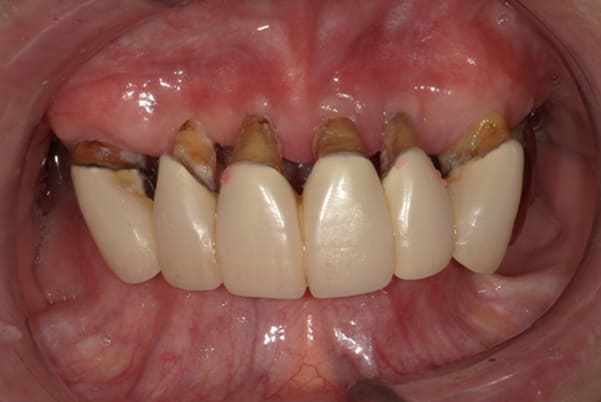

上前歯はブリッジの差し歯により根が折れ炎症を起こしお痛みのある状態でした。

原因は長期使用により下の義歯の歯が削れたことにより、下前歯が上前歯を突き上げ強い力が加わっていたことが根本的な原因と考えられます。

治療前は、奥歯が下がり、かみ合わせが乱れています。適切な入れ歯はそのままのかみ合わせで義歯を作るのではなく治療後のように、前歯から奥歯までのラインが真っすぐ揃った、かみ合わせの面を適切に付与し、よく咬め、残りの歯に負担がかからないかみ合わせとしました。

上顎治療前

-

上顎治療後

根のみの7本は虫歯にもなっており歯肉は腫れあがっています。

残りの歯もレントゲンで重度の歯周炎によりぐらぐらな状態でした。